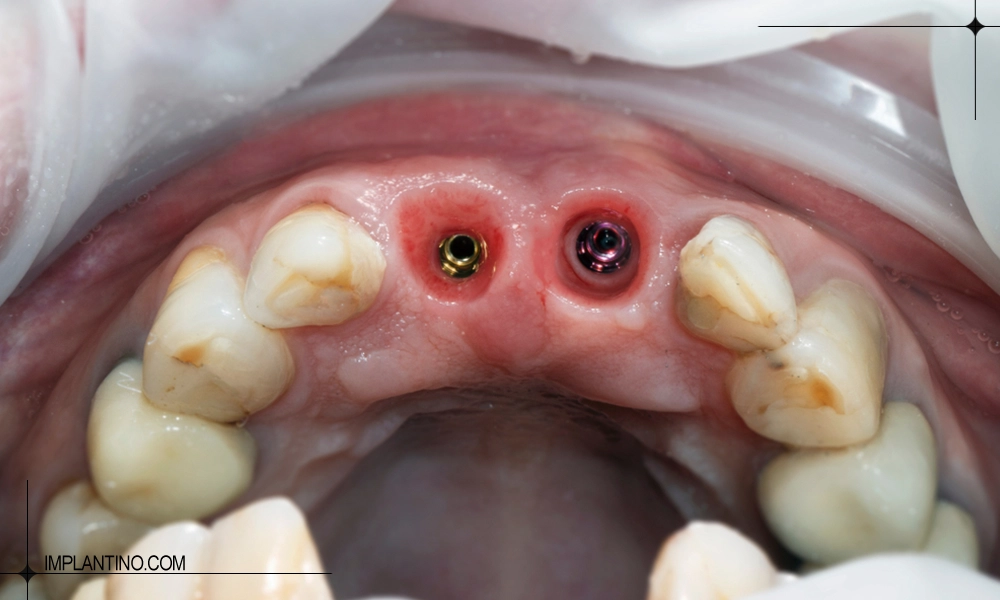

- برای فک بالا: ۴ تا ۶ ایمپلنت برای جایگزینی کامل دندان ها کافی است.

برای فک بالا، تعداد ایمپلنت مورد نیاز به تراکم استخوان و تعداد دندان های از دست رفته بستگی دارد. به طور معمول، برای جایگزینی کامل دندان های فک بالا بین ۴ تا ۶ ایمپلنت کاشته می شود. فک بالا به دلیل تراکم کمتر استخوان نسبت به فک پایین، نیازمند دقت بیشتری در تعیین محل و تعداد ایمپلنت است تا پروتز ثبات کافی داشته باشد و فشار جویدن به طور یکنواخت توزیع شود. در برخی موارد خاص و با تکنیک های پیشرفته مانند ایمپلنت زاویه دار، ممکن است حتی با ۴ ایمپلنت بتوان تمام فک را پوشش داد.

تعداد ایمپلنت برای فک بالا